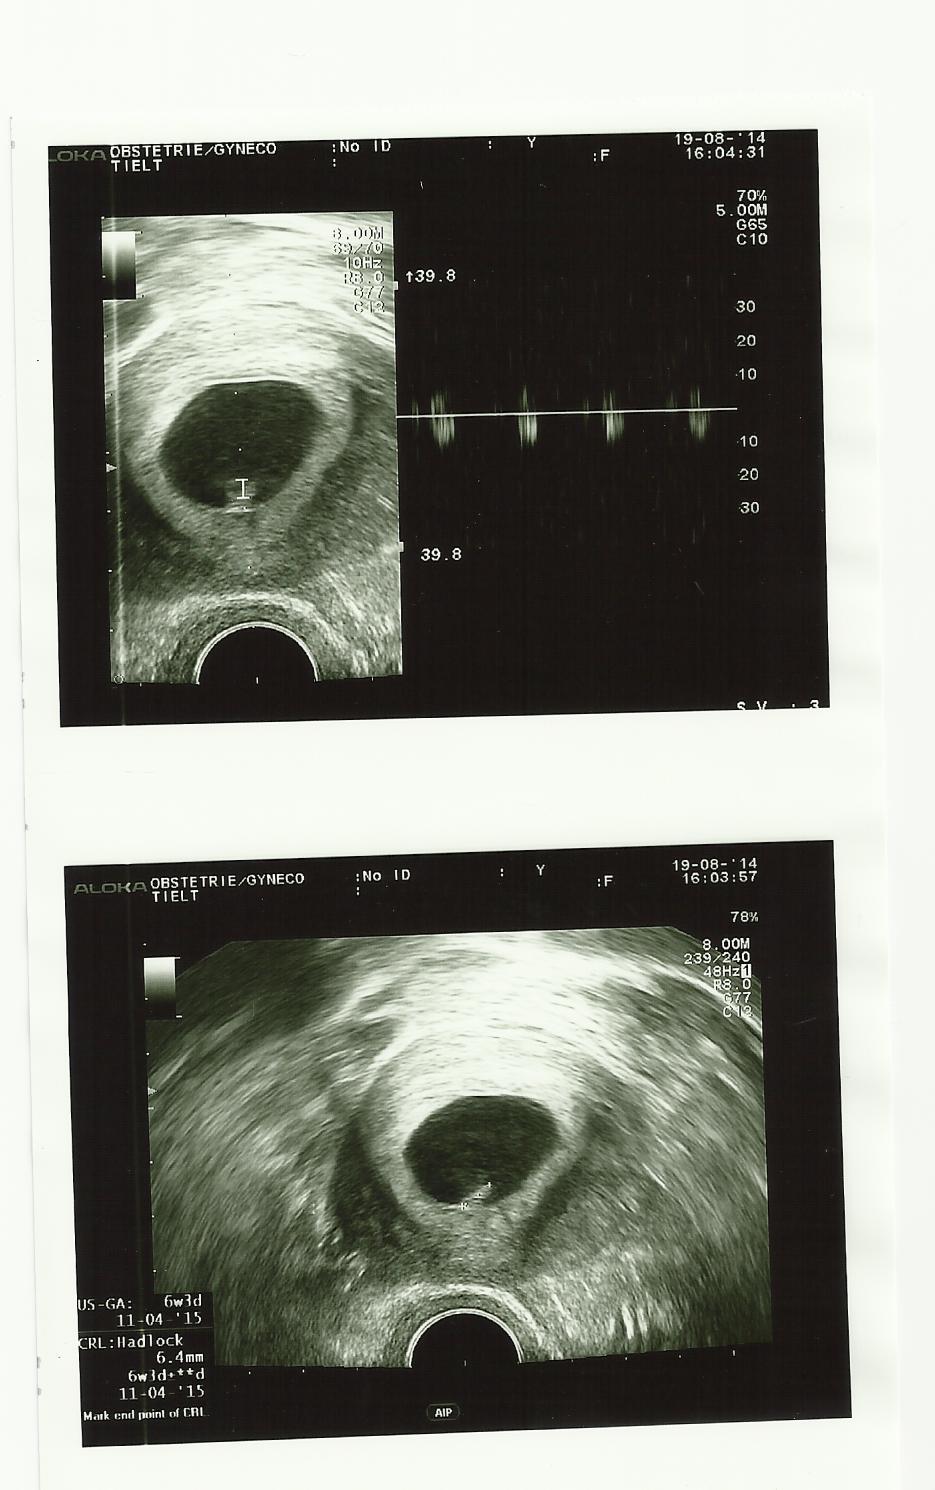

De gynaecologe vertelde me dat je al 6 weken 3 dagen oud was. Ze toonde me op de echo dat je momenteel 6.4 mm groot bent. Groei maar rustig verder, kleine schat! Ten slotte schatte ze jouw geboortedatum: 11 april 2015!

De grootste verrassing was echter toen dokter Servaes me vroeg om even te luisteren. Liefste schatteke, nog zo klein en toch… Ik kon jouw hartje al horen!